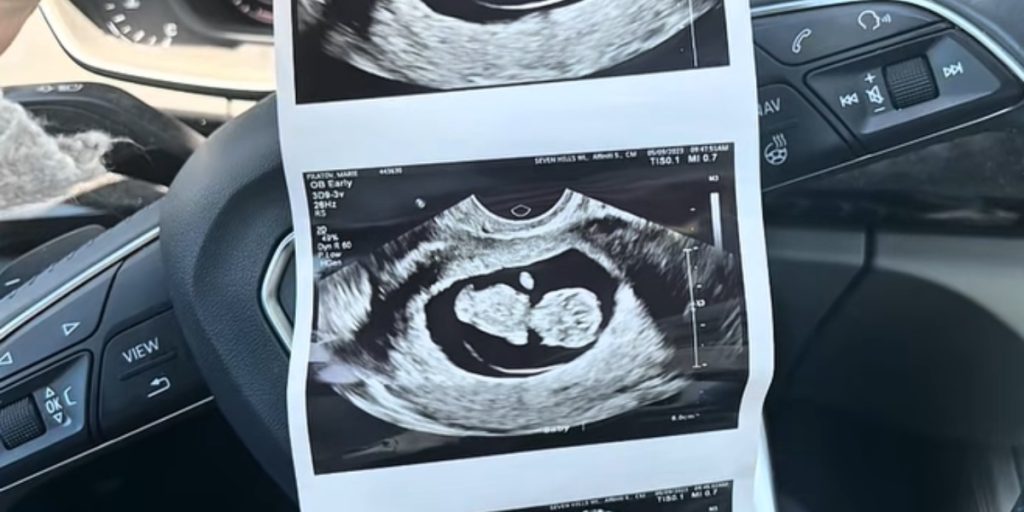

25-årige Marie Filatov fra Cincinnati har delt en video på TikTok under brugernavnet @mariemomlife, hvor hun fortalte om oplevelsen, da hun i 2022 var gravid med sin datter Myla. Videoen er på kort tid blevet set mere end 430.000 gange.

“Jeg var lykkelig over at skulle have mit første barn med min forlovede Jack. Alt virkede som en helt normal graviditet, indtil vi skulle til 20-ugers-scanningen,” sagde Marie til Newsweek.

Scanningen skulle være rutinemæssig, som alle gravide kvinder får midtvejs i graviditeten. Men for Marie blev det alt andet end en almindelig oplevelse. Hun husker tydeligt, hvordan lægen den dag vendte sig mod dem og sagde noget overraskende.

“Alt ser fint ud – der er bare én ting: Hun mangler sin venstre hånd,” sagde Marie.